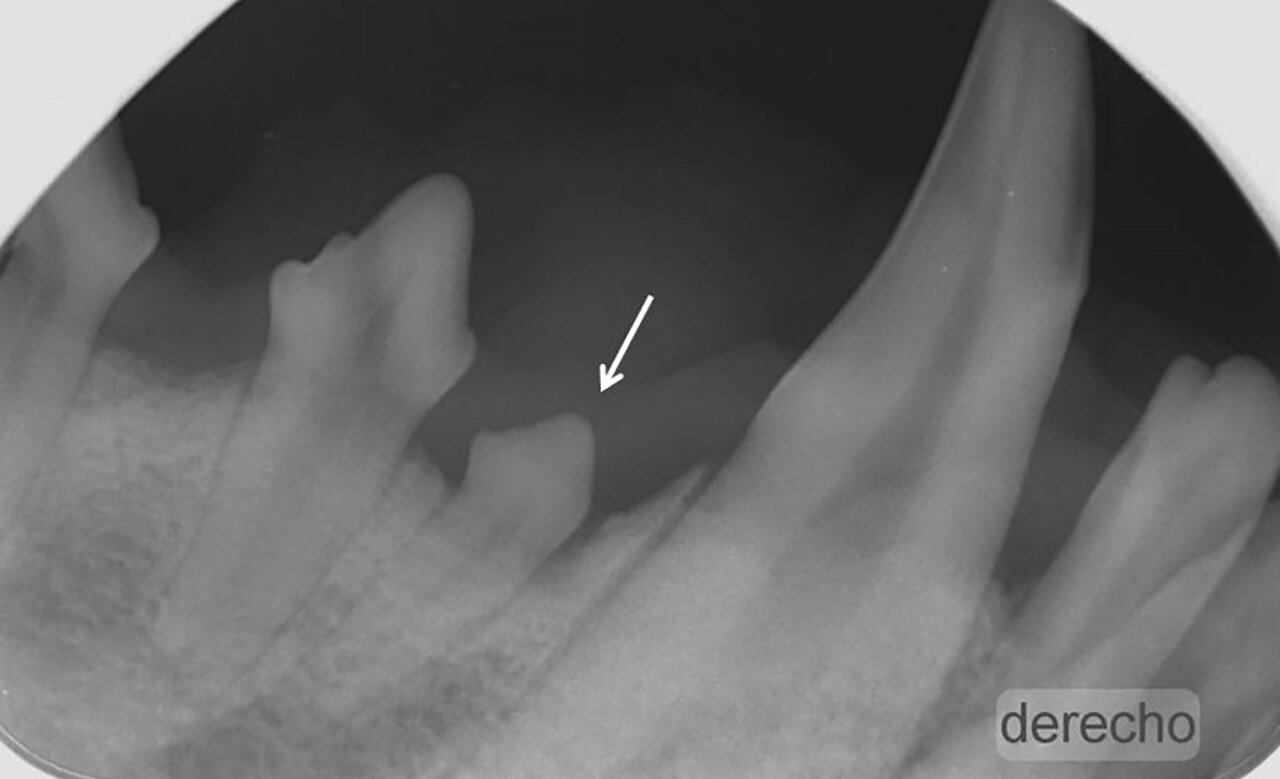

- Grado 2 (PD2): pérdida del soporte óseo menor al 25 % (imagen 7).

- Grado 3 (PD3): pérdida del soporte óseo de un 25-50 % (imagen 8).

- Grado 4 (PD4): pérdida del soporte óseo mayor de un 50 % (imagen 9).

Además de permitirnos evaluar el grado de enfermedad periodontal, también hace posible seleccionar el mejor tratamiento en función de su patología y las posibles complicaciones, como las fracturas mandibulares iatrogénicas en perros de talla pequeña con enfermedad periodontal PD4 (imágenes 10 y 11).